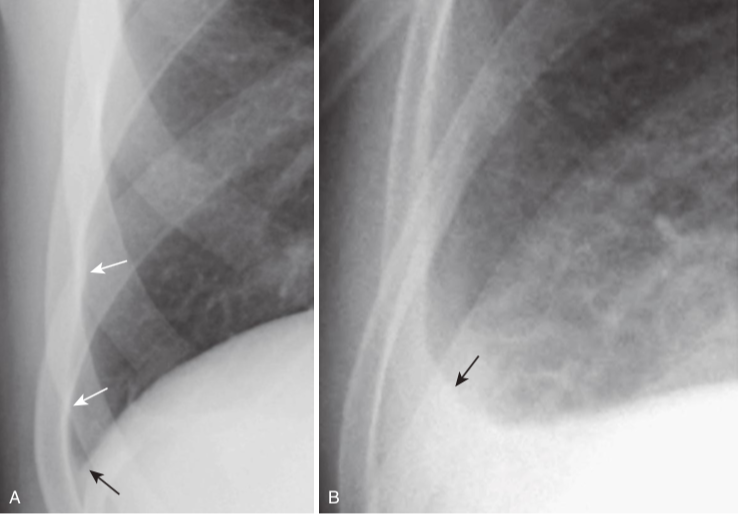

Hydropneumothorax.

hydropneumothorax produces an air-fluid level in the hemithorax marked by a straight edge and a sharp, air-over-fluid interface when the exposure is made with a horizontal x-ray beam (black arrows). This person was stabbed in the right side and there is a moderately large pneumothorax as shown by the visceral pleural white line (white arrows).